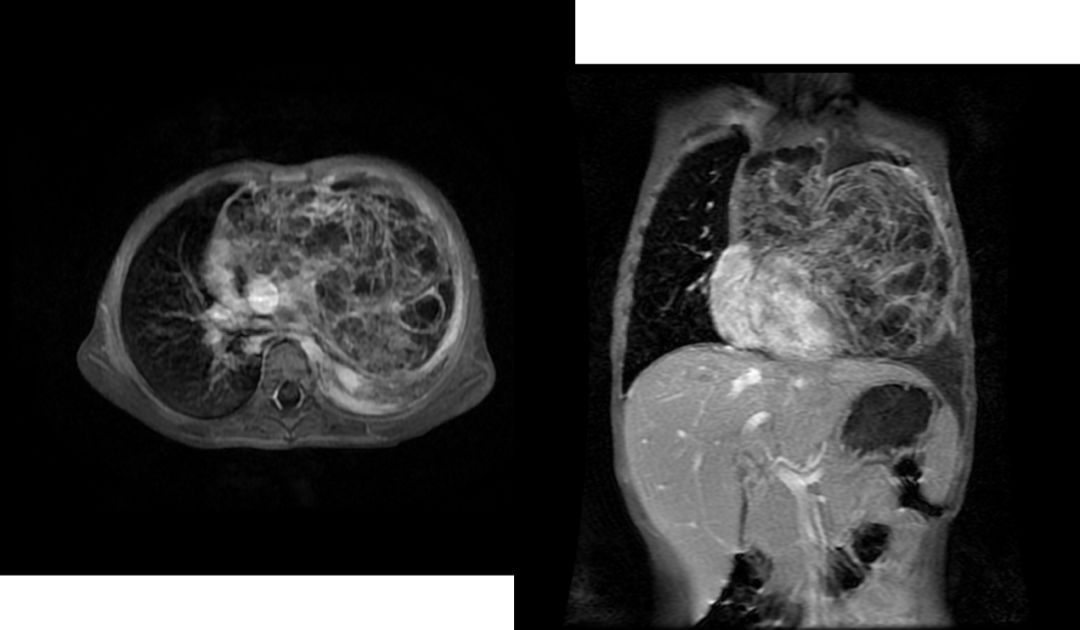

3.畸胎瘤

部位:前纵隔实性肿物;

密度:不均,可有脂肪、钙化、牙齿及骨骼影;皮样囊肿为液性密度,可见蛋壳样钙化;

形状:圆形或类圆形,边缘光滑;良性多;恶性者呈边缘不清,可坏死,周围脂肪间隙消失;

CT、MRI多数可明确诊断。

畸胎瘤影像学表现